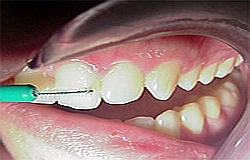

Zahnreinigung und Kontrolle

Die Kontrolle der Zahnfleisch Gesundheit geschieht in unserer Praxis durch objektive elektronische Längenmessung der Zahnfleischtaschen bei jeder professionelle Zahnreinigung. Somit kann man positive aber auch negativen Entwicklungen feststellen und anschließend gezielt und lokalisiert entgegenwirken.

Damit Ihre Zähne gar nicht erst defekt werden, reinigt ein fleißiges Prophylaxe Team Ihre Zähne mit sanftem Pulverstrahl und Polierbürste.